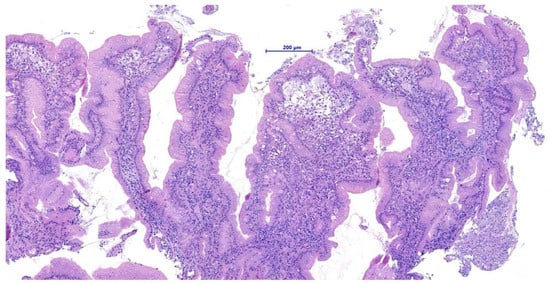

Endoscopic biopsies collected from this area revealed coalescent villi with thickened and edematous apices, without damage to the surface epithelium. Occasional glandular dilatation was observed, indicating mild epithelial injury. No lymphatic vessel dilation was present. Mucosal fibroplasia was mild. The number of intraepithelial lymphocytes was within normal limits, while the lamina propria showed moderate infiltration of lymphocytes and plasma cells, along with a mild increase in neutrophils. These findings were interpreted as consistent with a moderate chronic- active lymphoplasmacytic and neutrophilic enteritis with mild fibroplasia, suggestive of a post- inflammatory reparative phase, consistent with the resolution of previously diagnosed FGESF (Figure 4).

Figure 4. Histological section: moderate chronic-active lymphoplasmacytic and neutrophilic enteritis with fibroplasia H&E, 200×, scale bar = 200 µm.